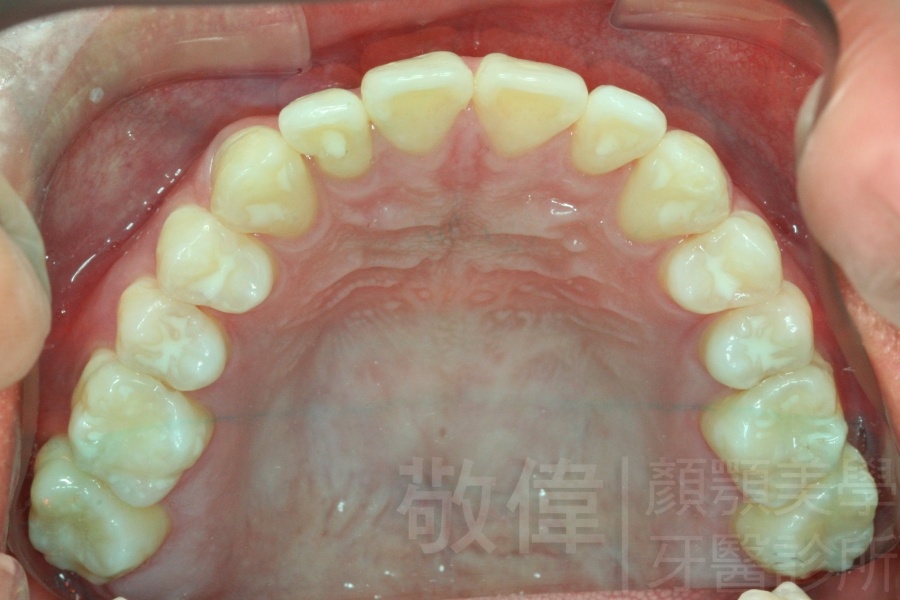

變臉矯正,原來戽斗妹跟大歪臉變成自信正妹

經由本院3D數影X光影像儀分析、與3D齒顎顏矯正技術,再配合口腔顎面正顎專科醫師施以正顎手術治療,雙方共同合作,使患者臉部外觀有很好的改善,大歪變小歪,產生了天南地北的大改變,她的人生也整個變得不一樣。

因為矯正與正顎手術的配合,使「戽斗妹」變成了「陽光正妹」,完全的改變了她的人生,在面對各種場合、與人交際都散發出自信微笑。所以,奉勸家長,如果小朋友有臉顎畸型的問題,應該考慮配合做這種簡單、安全、有效的正顎手術。